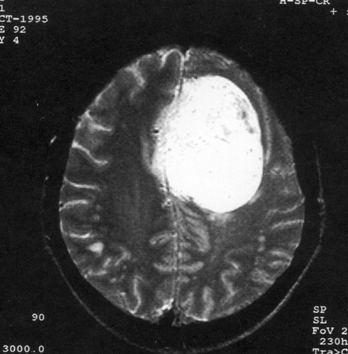

问题 病历摘要:??患者,男,40岁。发作性左下肢抽搐1年余,每次发作3~5分,每周发作1~2次。每次发作后感左下肢乏力,约半日后可自行恢复。既往身体健康。体检:神清,头顶部偏右有局限性骨性隆起(1.5×1.5cm),左鼻唇沟稍浅,伸舌居中。感觉、运动无明显异常。左浅反射减退,左下肢腱反射稍亢进,左Babinski征(-)。 术前的检查和治疗应包括下列哪些?提示:初步诊断考虑脑膜瘤,拟手术治疗。